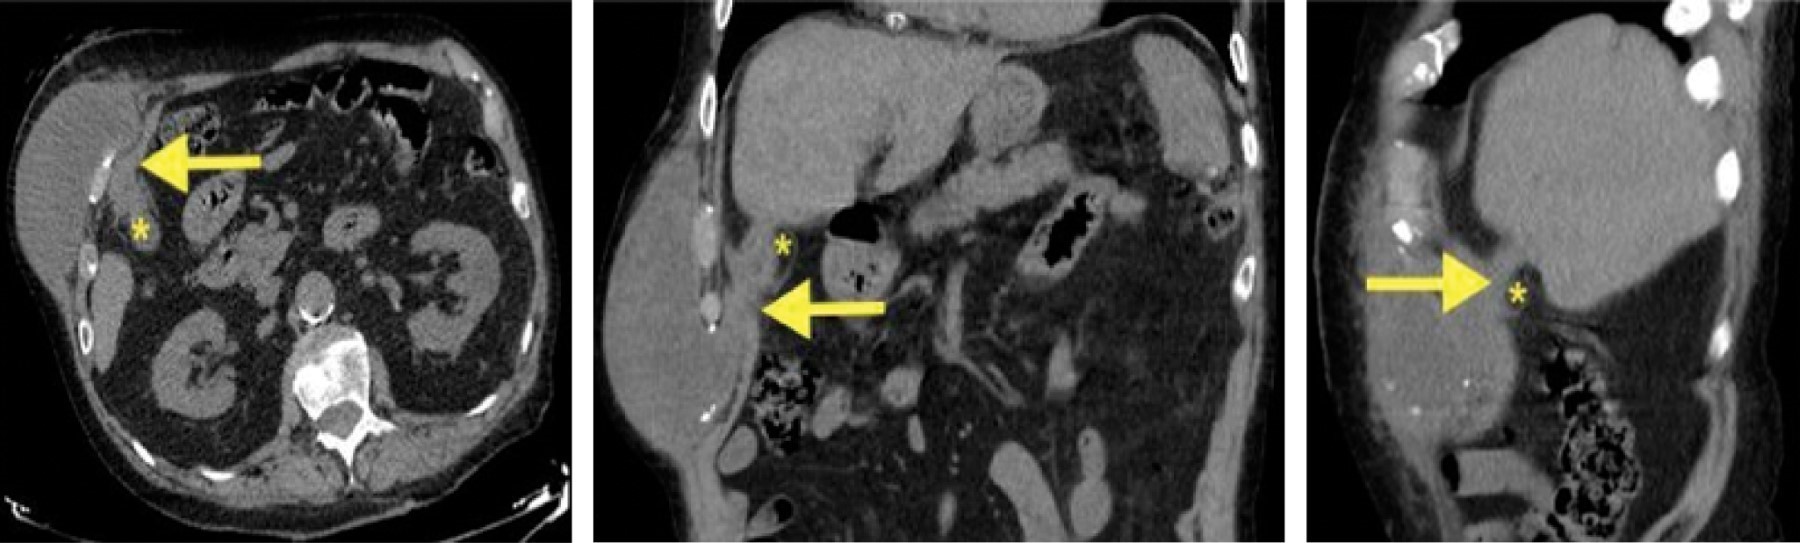

Case 5. A 75-year-old man had been operated on 30 years earlier for a gastric ulcer. He consulted for weight loss and a mass on the cranial end of the mid-laparotomy scar, painful, and not reducible on palpation. The abdominal CT scan showed a subcutaneous collection of 10 × 6 cm in trans parietal continuation with a gallbladder of irregular contours and thickened walls suggesting evolved cholecystitis. In addition, he reported a 9 mm focal lesion in segment IVb compatible in the clinical context with a hepatic abscess.

A percutaneous drainage of the abscess was performed, and AB treatment was given. A subsequent MRI cholangiography showed heterogeneous thickening of the gallbladder wall, adenopathy in the hepatic hilum, and the focal lesion in the hepatic segment IVb previously described (Figure 4). A biopsy of the hepatic lesion was performed, with an immunohistochemical result of metastatic adenocarcinoma of biliopancreatic origin. The PET-CT extension study showed pathological uptake in the gallbladder, hepatic hilum, segment IVb lesion, and a nodule in the right lung. Palliative chemotherapy and placement of a biliary stent were indicated, with immediate good evolution regarding the resolution of the septic picture and FCC. He died 14 months after the diagnosis of gallbladder neoplasm.

Figure 4